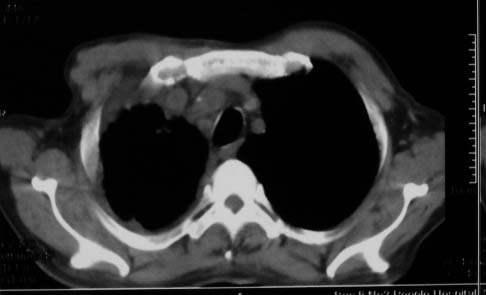

影象表现:右肺上叶大片状、网格状及索条致密影,蜂窝影,其内参杂斑点状小结节,密度不均匀,内见含气支气管像,纵隔内见肿大淋巴结.

抗感染病变无明显改善,右上叶大片状增弥不均匀病灶,夹杂网状及支气管充气像,肺门纵隔淋巴结肿大,右侧胸腔积液。考虑1混合感染伴肺间质改变[警惕特殊感染,如真菌]。2细支气管肺泡癌。建议结合临床及进一步检查[如痰,胸水脱落细胞检查及支气管镜检灌洗或穿刺活检

影象表现:右肺上叶大片状、网格状及索条致密影,蜂窝影,其内参杂斑点状小结节,密度不均匀,内见枯枝样含气支气管像,纵隔内见肿大淋巴结.胸膜广泛增厚,前胸壁似受累.少量胸腔积液.纵隔内淋巴结的直径>1.5cm.右侧胸廓体积缩小.考虑:1 肺结核合并间质纤维化 2 细支气管肺泡癌

右肺上叶大片状、网格状及索条致密影,蜂窝影,其内参杂斑点状小结节,密度不均匀,内见枯枝样含气支气管像,纵隔内见肿大淋巴结.胸膜广泛增厚,前胸壁受累增厚.少量胸腔积液.纵隔内淋巴结的直径>1.5cm.右侧胸廓体积缩小.考虑: 细支气管肺泡癌并肺内癌性淋巴管炎。